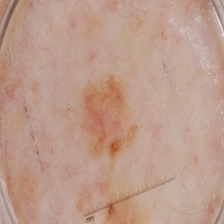

malignant

564.jpg

224x224px